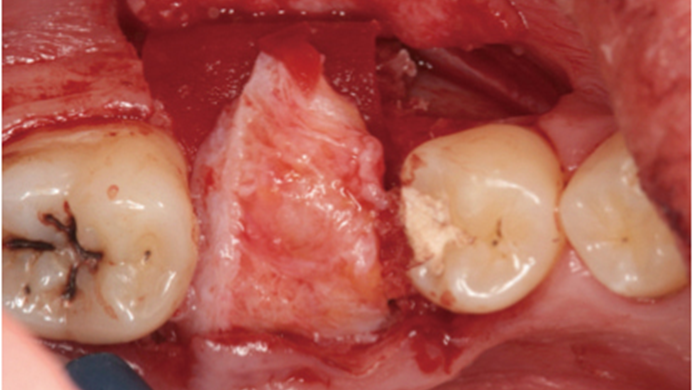

Clinical case: # 46 implant placement & GBR using i-Gen membrane for significant vertical resorption & mixed bone defect

- Courtesy of Dr. Iulian Filipov, Romania -

AnyRidge, mandibular posterior, i-Gen, resorption, bone defect, bone regeneration, space management, #46, GBR, Dr. Iulian Filipov

AnyRidge implant system, i-Gen